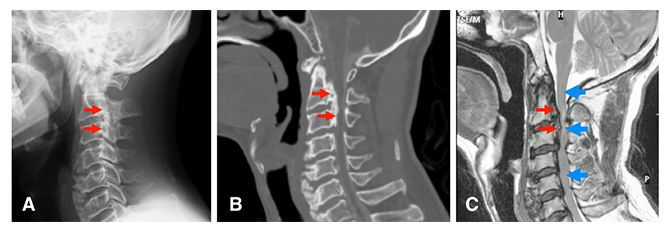

図1 後縦靭帯骨化症(OPLL)の画像所見

同一患者の頚部(首)の側面像。左が腹側、右が背側。

- (A)単純X線像。赤矢印で示した部分が骨化した靭帯。

- (B)同じ部位のCT像。第2頚椎椎体から第3頚椎椎体の背側にかけて、骨化した後縦靭帯(赤矢印)が見られる。

- (C)同じ部位のMRI像。青矢印で示した部分が椎体の背側にある脊髄。骨化した靭帯により圧迫されて、特に上から2番目の青矢印周辺で細くなっている。